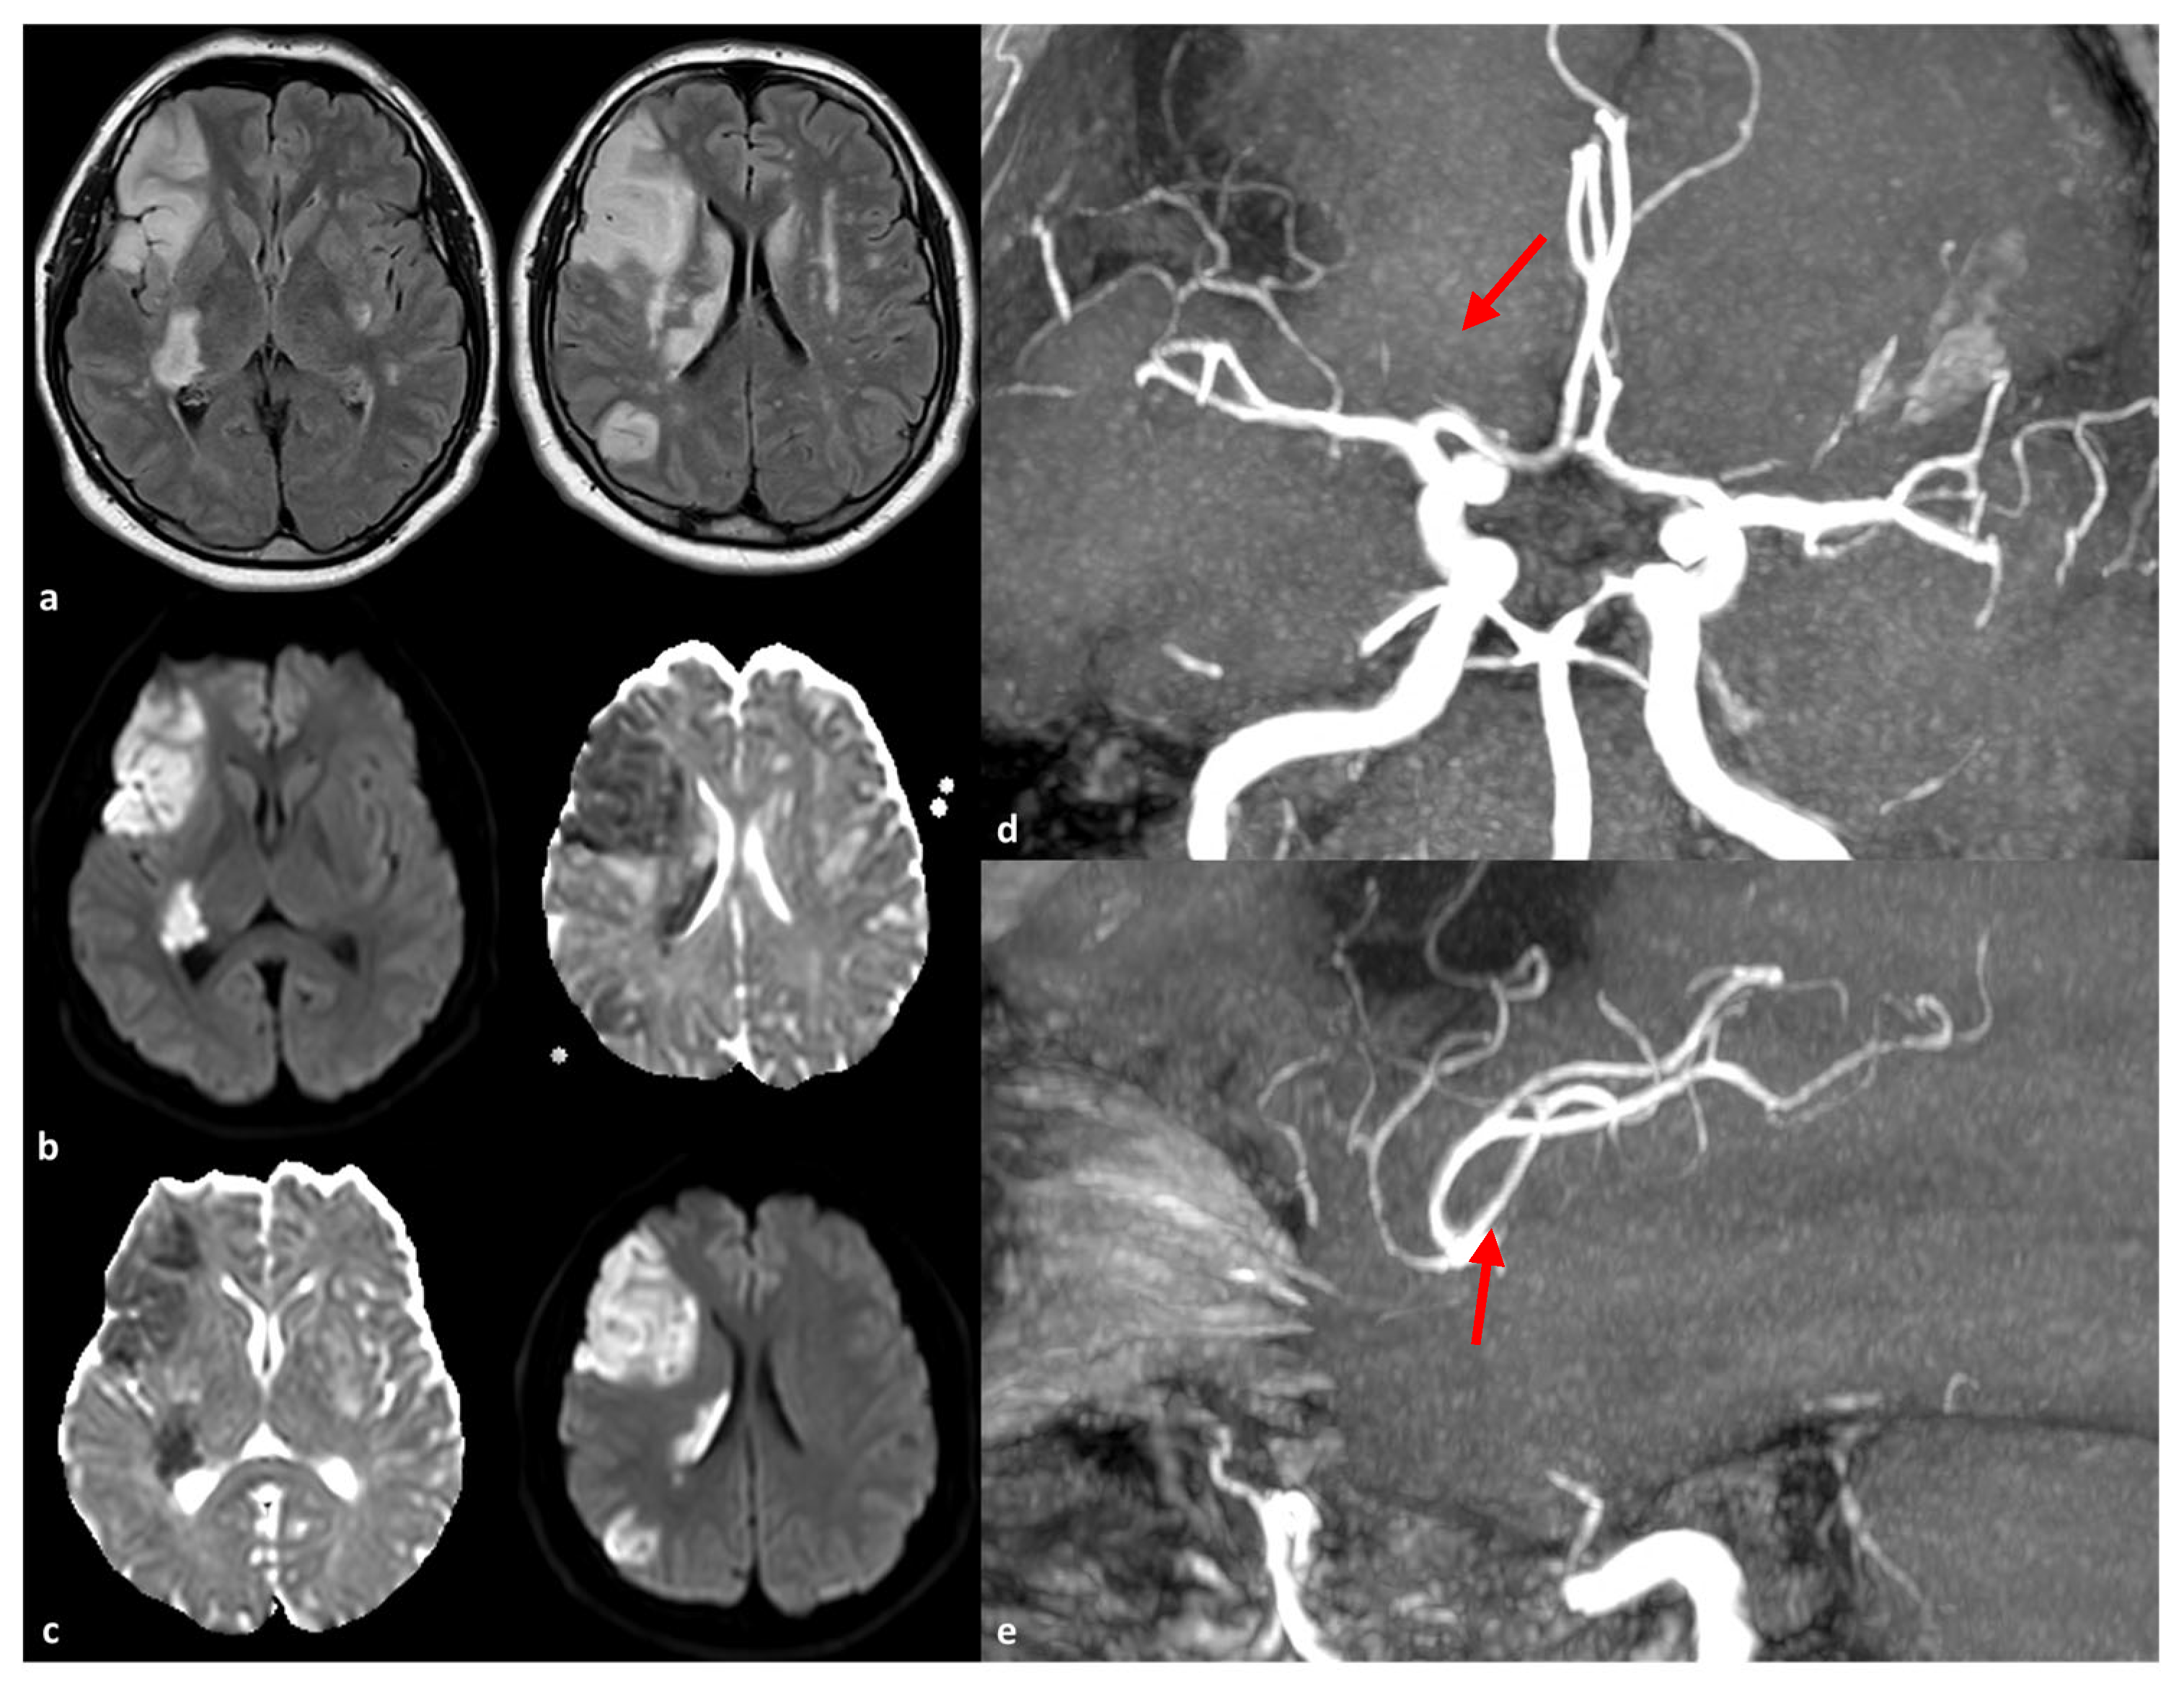

- Saito, S.; Hosoki, S.; Yamaguchi, E.; Ishiyama, H.; Abe, S.; Yoshimoto, T.; Tanaka, T.; Hattori, Y.; Liao, Y.C.; Lee, Y.C.; et al. Blended Phenotype of NOTCH3 and RNF213 Variants With Accelerated Large and Small Artery Crosstalk: A Case Report and Literature Review. Neurol. Genet. 2024, 10, e200176. [Google Scholar] [CrossRef]

| c.14576G > A | 29 | 124 | 384 | Japan | Carrier rate in CADASIL patients with intracranial stenosis: 23.5% (4/17) vs. 1.9% (2/107) without stenosis (p = 0.0032). Higher frequency of territorial infarction in carriers (75.0% vs. 20.0%, p = 0.0410). 2.6% of control population identified as carriers of the c.14576G > A variant. 21.9% of sporadic intracranial stenosis patients exhibited this variant in the Japanese population [5]. |

| c.14429G > A (p.Arg4810Lys) | 29 | 124 | 384 | Japan | Found in 4.8% (6/124) of CADASIL patients; higher than 1.5% in the general population. Present in 80–90% of familial moyamoya disease cases; significant risk factor for intracranial artery stenosis [12]. |